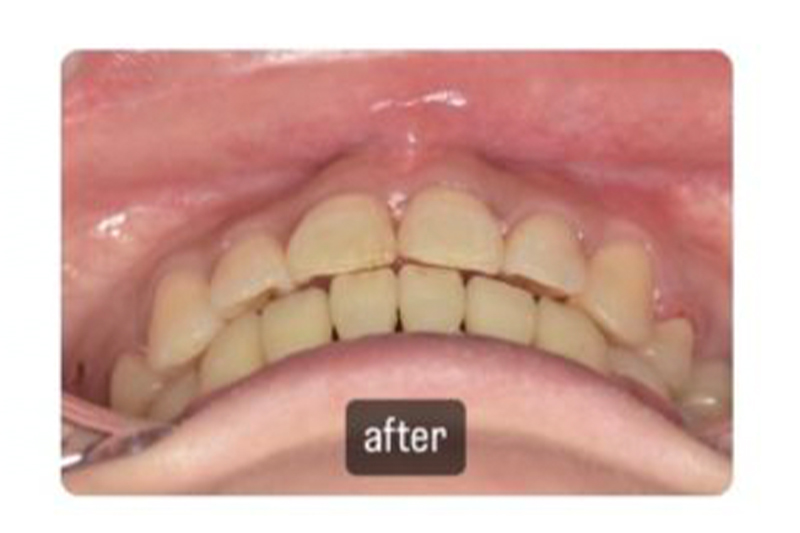

術前

術後

| 年代/性別 | 35歳/女性 |

|---|---|

| 主訴 | 歯のガタつきを治したい |

| 治療方法 | インビザライン(マウスピース矯正)での治療 |

| 費用 | 90万円 |

| 備考 | 高度な診断力を要する為、診断能力の無い歯科医師に当たると失敗するリスクがある。 |

ワイヤー矯正は絶対に嫌だということで、インビザラインで治療しましたが、快適に治療できたようで満足されていました。